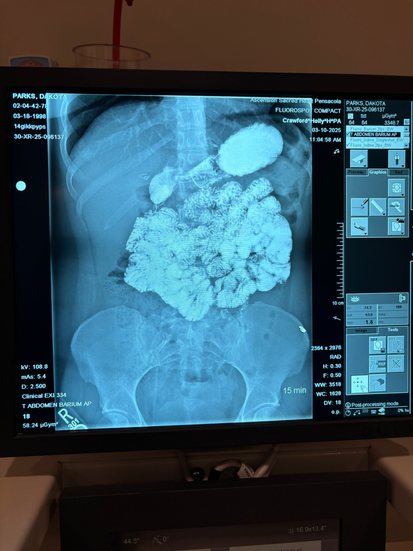

So far, I’ve been diagnosed with bile reflux gastritis—which slowly corrodes your stomach lining day by day, leaving you nauseous, unable to eat, nutrient deficient, brain fogged, with random excruciating rib pain and feeling utterly exhausted until you either vomit yellow bile nonstop or fill your stomach with nutritional or medicinal binders to soak up the bile. It has no cure and very little research funding, but online support groups have taught me how to manage it. Then there are the weird symptoms no one can explain like the chronic dry eye and my eyes swelling up like painful, red puffy balloons for days and weeks at a time no matter if I’m home or traveling. I’ve also been diagnosed with endometriosis, potentially mast cell activation syndrome, and the devilish twin diagnoses of POTS and Ehlers-Danlos. While we still have more testing and answers to gather, let me tell you though, the taste of a diagnosis on your lips after years of screaming and demanding with profit-driven doctors who truly don’t care about long-term health that something is seriously wrong… a delightful benediction in a silver chalice. I have finally found an arsenal of feminist, badass female doctors who are listening to me and demanding the care I deserve.

Last week, I had endometriosis surgery to check how badly it was growing onto my colon and GI tract to see if it would alleviate my GI symptoms and to potentially receive a hysterectomy. Luckily, it was stage 2 endo instead of stage 4, so they removed my fallopian tubes (hell yeah voluntary female sterilization in Trump’s America), a golf ball-sized endometrioma from one ovary, another small cyst from the other ovary, and a lot of scar tissue. While I got to keep my old trusty uterus for now, this week has been hell. I did not recover from surgery like most people.